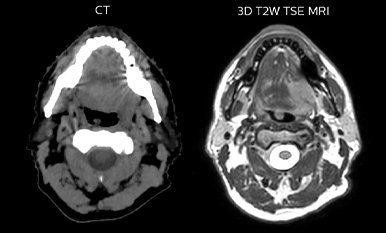

Comparison of CT simulation scan

Comparison of CT simulation scan (left) and T2W 3D MRI (right)